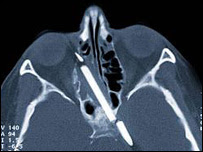

A woman in Germany who has spent 55 years with part of a pencil inside her head has finally had it removed.

Margret Wegner fell over carrying the pencil when she was four. It punctured her cheek and part of it went into her brain, above the right eye.

The 59-year-old has suffered headaches and nosebleeds for most of her life.

Surgeons in Berlin were able to remove most of the pencil in a two-hour operation, but a 2cm section was so embedded it was impossible to remove.